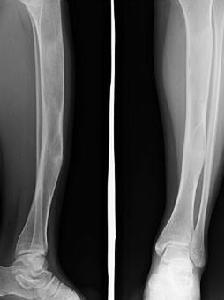

X線檢查,單髮型纖維異樣增殖症病變部位在髓腔內,長管狀骨的乾骺端或骨幹,中心位或偏心位,病變的X線表現為模糊的髓腔內放射透明(低密度)區,常被形容為“磨砂玻璃狀”,其中可見不規則的骨紋理,骨質有不同程度的擴張,骨皮質變薄,病變區與正常骨質間界線明顯,可看到反應性硬化緣帶,不產生骨膜反應。病變部位在股骨頸或股骨上端可發生鐮刀狀變形,形容為“牧羊杖”畸形。脊柱的病變界線亦清楚,膨脹,X線有低密度區,其內部呈分隔狀或條紋狀,可因病理性骨折而塌陷。局限性病變僅發生在乾骺端,如股骨近端乾骺端,廣泛性病變常侵犯長骨的一端與大部分骨幹,骨質向外明顯突出,骨皮質薄厚不均,或向一側彎曲變形,如發生在脛骨骨幹。發生病理性骨折後骨膜產生新生骨,使骨皮質增厚硬化。病變很少侵犯骨骺軟骨,僅在骺線閉合後,才侵入骨端。

多髮型纖維異樣增殖症病變常侵犯數骨,並有侵犯鄰近數骨的現象,如侵犯同側的髂骨、股骨、脛骨及腓骨,髂骨的病變系溶骨性,呈較大的多囊狀,其中可見骨紋理,有不同程度的骨質膨脹。四肢長骨的病變常累及骨的全部,髓腔寬窄不均,其增寬處骨皮質變薄並擴張,髓腔內紋理消失,呈磨砂玻璃狀,有的部位骨質高度膨脹,其中有囊狀表現,常發生病理性骨折。顱骨病變中,顱底骨質緻密,枕、顳骨變形,呈緻密與疏鬆相混的陰影。